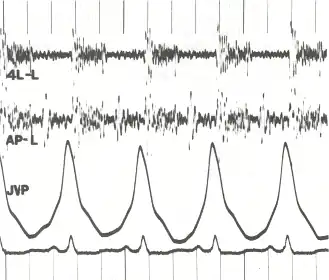

![]() Phonocardiogram and jugular venous pulse tracing from a middle-aged man with pulmonary hypertension (pulmonary artery pressure 70 mm Hg) caused by cardiomyopathy. The jugular venous pulse tracing demonstrates a prominent a wave without a c or v wave being observed. The phonocardiograms (fourth left interspace and cardiac apex) show a murmur of tricuspid insufficiency and ventricular and atrial gallops.[1] | |